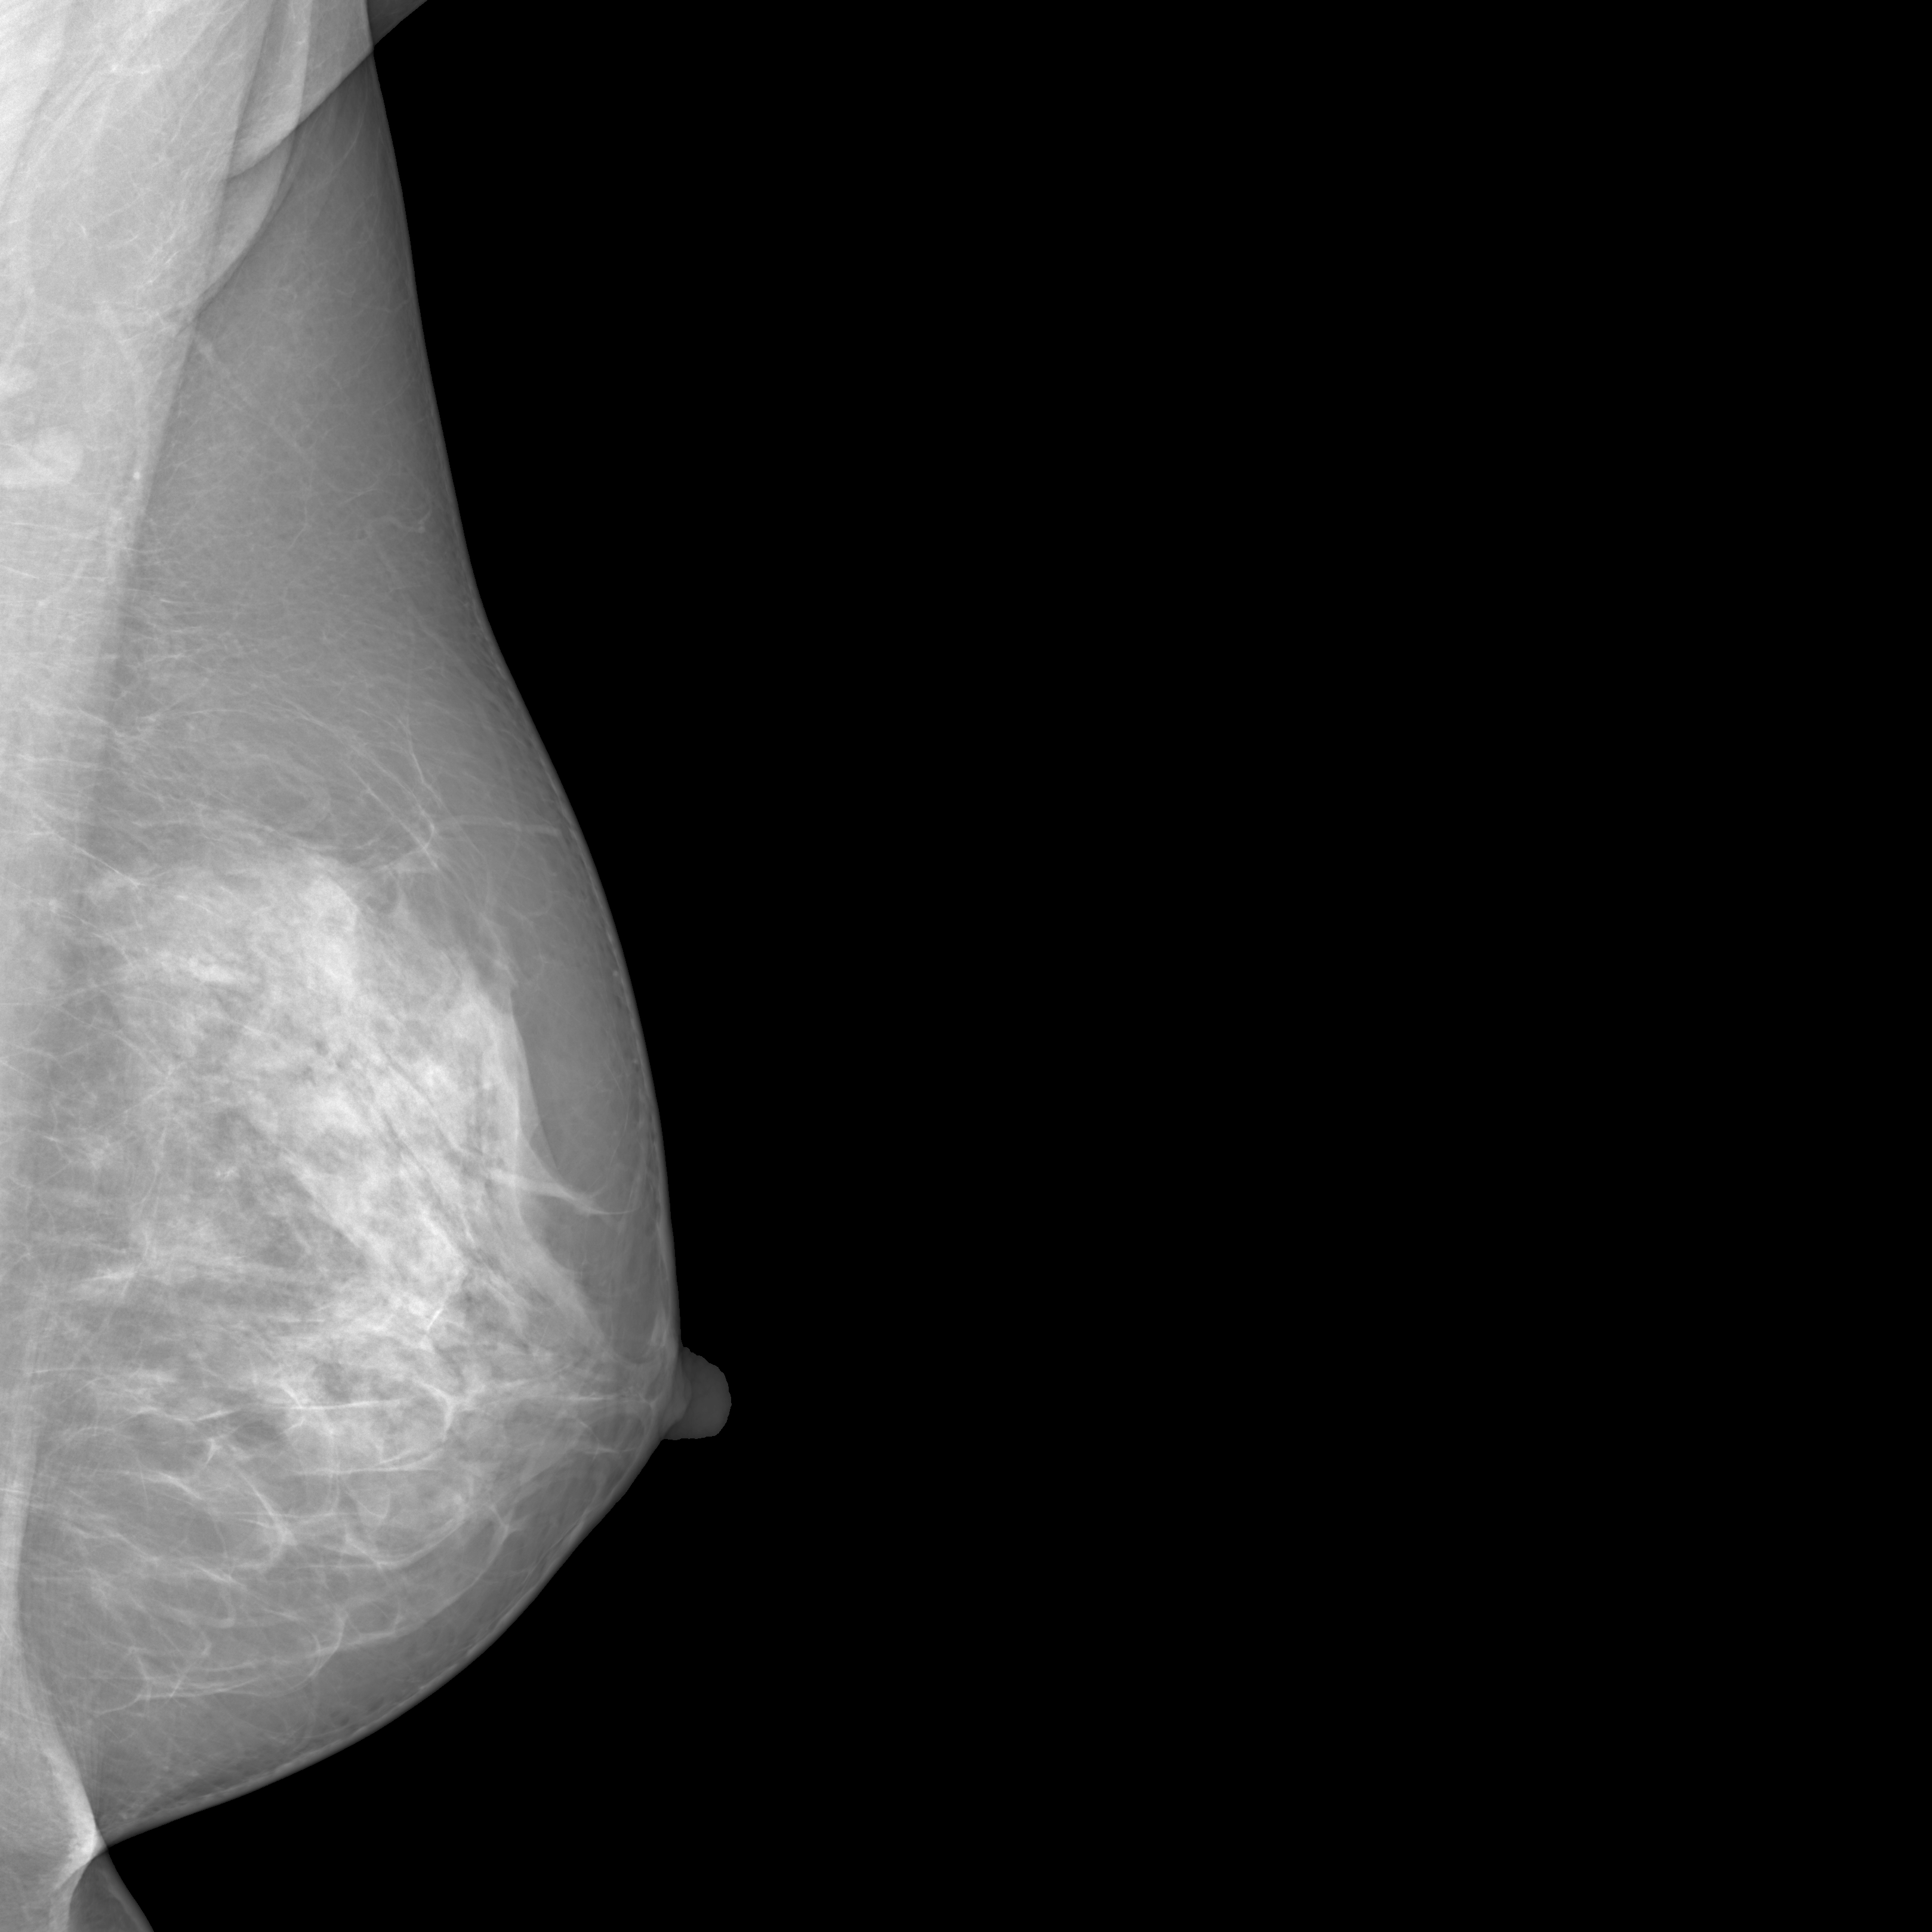

To overcome these challenges, this paper introduces MAMmography ensemBle mOdel (MAMBO), a novel approach that leverages an ensemble of diffusion models to generate mammography images at their native resolution. MAMBO uses a patch-based approach for generation which is conditioned both on local and global (full-image) context. In a nutshell, MAMBO involves the development of three distinct models: the first generates “standard”-resolution ( pixels) images to provide global context; the second increases the resolution to create local context for the target patch; and the third combines the outputs of both models to guide the generation of high-resolution patches, which are then reconstructed into a full-resolution synthetic mammogram. An example of a synthetic image generated by MAMBO is shown in Fig. 1. The image presents details at multiple resolutions, corresponding to the global and local contexts, and individual patch at full resolution. To the best of our knowledge, this is the first work to propose a diffusion model approach for generating very high-resolution synthetic mammograms.

What MAMBO can achieve in terms of qualitative results is presented in Fig. 1 and Fig. 3(d). MAMBO is able to generate high-quality images that are visually indistinguishable from the originals, representing plausible mammogram data to layman eyes. Results are also validated with expert radiologists, with quantitative results shown in Sec. 4.2.

Fig. 3(d) illustrates what MAMBO can achieve in terms of whole mammogram generation. When using global and local context data extracted from an original image, the denoised image (Fig. 3(b)) is difficult to distinguish from the original (shown in Fig. 3(a)). When providing only the original global context and generating local context and target patches from noise, we still observe good results, as we show in Fig. 3(d).